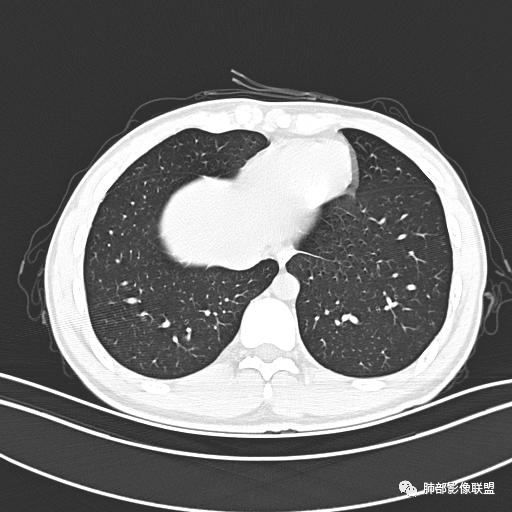

男,19岁

主  诉:发热、全身皮疹2天。

现病史:患者源于2天前受凉后出现发热,最高体温为38.5℃,且颜面部出现少量皮疹,无鼻塞、流涕、咳嗽、咳痰,未在意而未作特殊处理,次日全身皮疹逐渐增多至全身,伴轻度瘙痒,在当地卫生所给予抗病毒、抗感染治疗(具体用药不详)体温有所下降,但皮疹无明显消退,无腹痛、头痛,食欲无明显减退,为进一步诊治,遂于今日急来我院求治,患者目前精神尚可,体力正常,食欲正常,睡眠正常,体重无明显变化,大便正常,排尿正常。

小强:青年,发热,皮疹;双肺散在结节,周围磨玻璃,点晕征,疱疹病毒感染,鉴别荚膜组织胞浆菌,结核。 大雄:青年,急性起病,发热伴全身皮疹2天,抗病毒治疗体温有下降。双肺随机分布大小不等类圆结节,“点晕征”。考虑水痘-疱疹病毒(VZV)血播询问接触史,查体皮疹分布以及形态基本可诊断。 王开金江津中心医院呼吸科:青年男性,起病急,病程短,以发热,皮疹为首发症状,感染指标以单核细胞升高为主,胸部ct双肺多发结界,周围有晕,点晕表现,随机分布,同意於老师意见,水痘疱疹病毒血流感染累及肺。 王秀仙:双肺多发大小不等结节,周围有晕,边缘模糊,呈点晕征表现。青年,急性起病,发热伴全身皮疹2天,抗病毒治疗体温有下降。考虑疱疹病毒。鉴别荚膜组织胞浆菌。 傅昌瑜:19岁男性,发热、全身皮疹2天,单核细胞增高,双肺多发结节,结节边缘见边界不清磨玻璃影。点晕征+发热、全身皮疹+单核细胞增高——考虑水痘-带状疱疹病毒肺炎。 一切∮随缘:年轻男性,发热,皮疹两天,实验室,CRP,PCT增高,影像:双肺多发散在磨玻璃结节,边界欠清,大小不等,呈点晕征改变,以血管束周围分布为主,局部血管束略增粗,其它无明显改变,考虑:1:病毒性肺炎(水痘疱疹病毒?不知道皮肤有无改变)2:真菌(组织胞浆菌,血管侵袭性肺曲霉)3:GPA4:寄生虫(实验室没有看到嗜酸细胞增高) 赵山河:双肺散在结节,周围有晕,边缘模糊,呈点晕征表现。青年,急性起病,发热伴全身皮疹2天,抗病毒治疗体温有下降。考虑水痘—疱疹病毒感染。洪桥爱:青年男性,发热、皮疹2天,伴瘙痒,皮疹于面部首发,之后进展至全身,虽然没有对皮疹进行描述,但是从出疹时间及皮疹进展情况,伴瘙痒,应该就是个水痘患者;CT提示双肺随机分布结节影,部分结节伴有边界不清晕征,考虑水痘血播肺。 刘强:年轻男性,急性起病,皮疹,发热,抗感染治疗体温下降,说明有效。影像表现为散在点晕征,感染类疾病谱(疱疹病毒,真菌,结核),结合年龄,皮肤皮疹,考虑水痘-疱疹病毒性肺炎。 小兜:男性,19岁,发热皮疹两天,颜面部至全身,CRP,降钙素及单核增高。CT示双肺散在小结节,周围伴磨玻璃影,点晕征,考虑为水痘-带状疱疹病毒(varicella-zoster virus,VZV)肺炎 必有路:青年,皮疹+发热+“点晕征”→水痘-疱疹病毒(VZV) 许慧良:青年男性患者,发热、皮疹2天,体温最高38.5℃,第3天皮疹扩展至全身,伴瘙痒,胸部CT:双肺多发随机分布的小结节,结节周边见边界模糊的晕征,考虑水痘病毒感染流心明智:男,19,急性起病,发热伴全身皮疹2天。出疹顺序头→全身,抗病毒有效。胸部CT:两肺多发大小不等类圆形实性小结节影,随机分布,结节周围环绕GGO,边界模糊,呈点晕征。出疹特点是关键,未提示。考虑:血播病毒性肺炎,水痘-疱疹病毒?麻疹?鉴别荚膜组织胞浆菌、TB、血管炎、寄生虫等。 浪迹天涯:病灶多为5-10mm大小结节,结节周围可见磨玻璃样的晕环,常多发,可分布于肺内任何区域,考虑水痘—带状疱疹病肺炎如果短时间内有新的一个区域浸润,更加能说明,